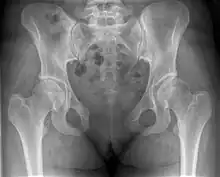

| Post traumatic pubic symphysis diastasis | |

X-ray

An X-ray film obtained in the AP view of the pelvic inlet and outlet will show a marked gap between the pubic bones.[3] A normal pelvis will show a gap that is 4–5 mm. However, in pregnancy the hormonal influences cause relaxation of the connecting ligaments and the bones separate up to 9 mm. A gap measuring greater than 10 mm indicates a pathological process.[3]

In addition, a view in the "flamingo stance" can be obtained to demonstrate the instability of the joint. This position consists of the patient standing with weight on one leg and the other bent.[6] A vertical displacement of more than 1 cm is an indicator of symphysis pubis instability.[7] A displacement of more than 2 cm usually indicates involvement of the sacroiliac joints.[3]